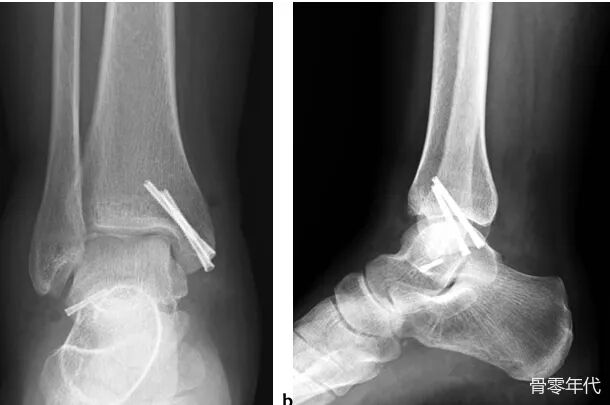

一名34岁的女性在踝关节内翻扭伤后立即入住我们的急诊科。就诊时,她无法负重,脚踝严重肿胀。主动和被动踝关节运动疼痛且受限。内踝和外踝均有压痛。神经血管检查结果正常。踝关节的直接放射学检查显示移位的内踝骨折和腓骨尖端的骨碎片(图1a,1b)。此外,斜X光片更清楚地描绘了碎片。为了了解损伤模式,进行了进一步的计算机断层扫描(CT)检查。CT显示该片段在 ATFL附着时从距骨撕脱(图 2a、2b、2c)。由于患者有移位的内踝骨折和踝关节不稳定,因此计划手术固定骨折。

术后影像学